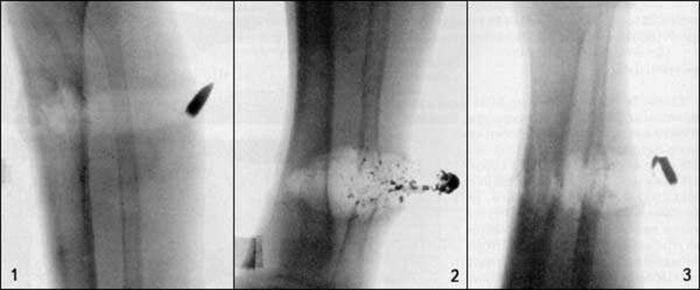

В настоящее время в военных конфликтах так же используются так называемые малоимпульсные патроны 5.45х39 мм или 5.56х45 НАТО. При попадании в тело, такие патроны начинают кувыркаться и вызывают обширные внутренние повреждения.

Как говорят судмедэксперты, убивает не пуля, а повреждения, которые она наносит. А повреждения эти делятся на два типа: ущерб от самой пули, разрывающей ткани и ломающей кости, и ущерб от энергии пули. Дело в том, что наши клетки наполнены жидкостью и огнестрельное ранение сопровождается гидроударом. От этого происходит повреждение нервных окончаний и вторичный разрыв тканей, когда пуля уже прошла дальше по раневому каналу.